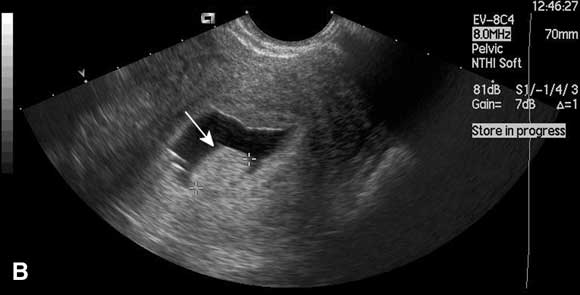

Saline infusion sonohysterography

In this technique, saline is instilled transcervically into the uterine cavity to distend the uterus and increase contrast, and the cavity is visualised using ultrasound (Box). Saline infusion sonohysterography is more accurate than transvaginal ultrasound alone in diagnosing submucous fibroids and endometrial polyps in women with abnormal uterine bleeding,12 and can be performed in the outpatient clinic. An alternative form of imaging is diagnostic hysteroscopy, but this is invasive and often performed under general anaesthesia. Use of saline infusion sonohysterography has been shown to reduce the need for diagnostic hysteroscopy.13